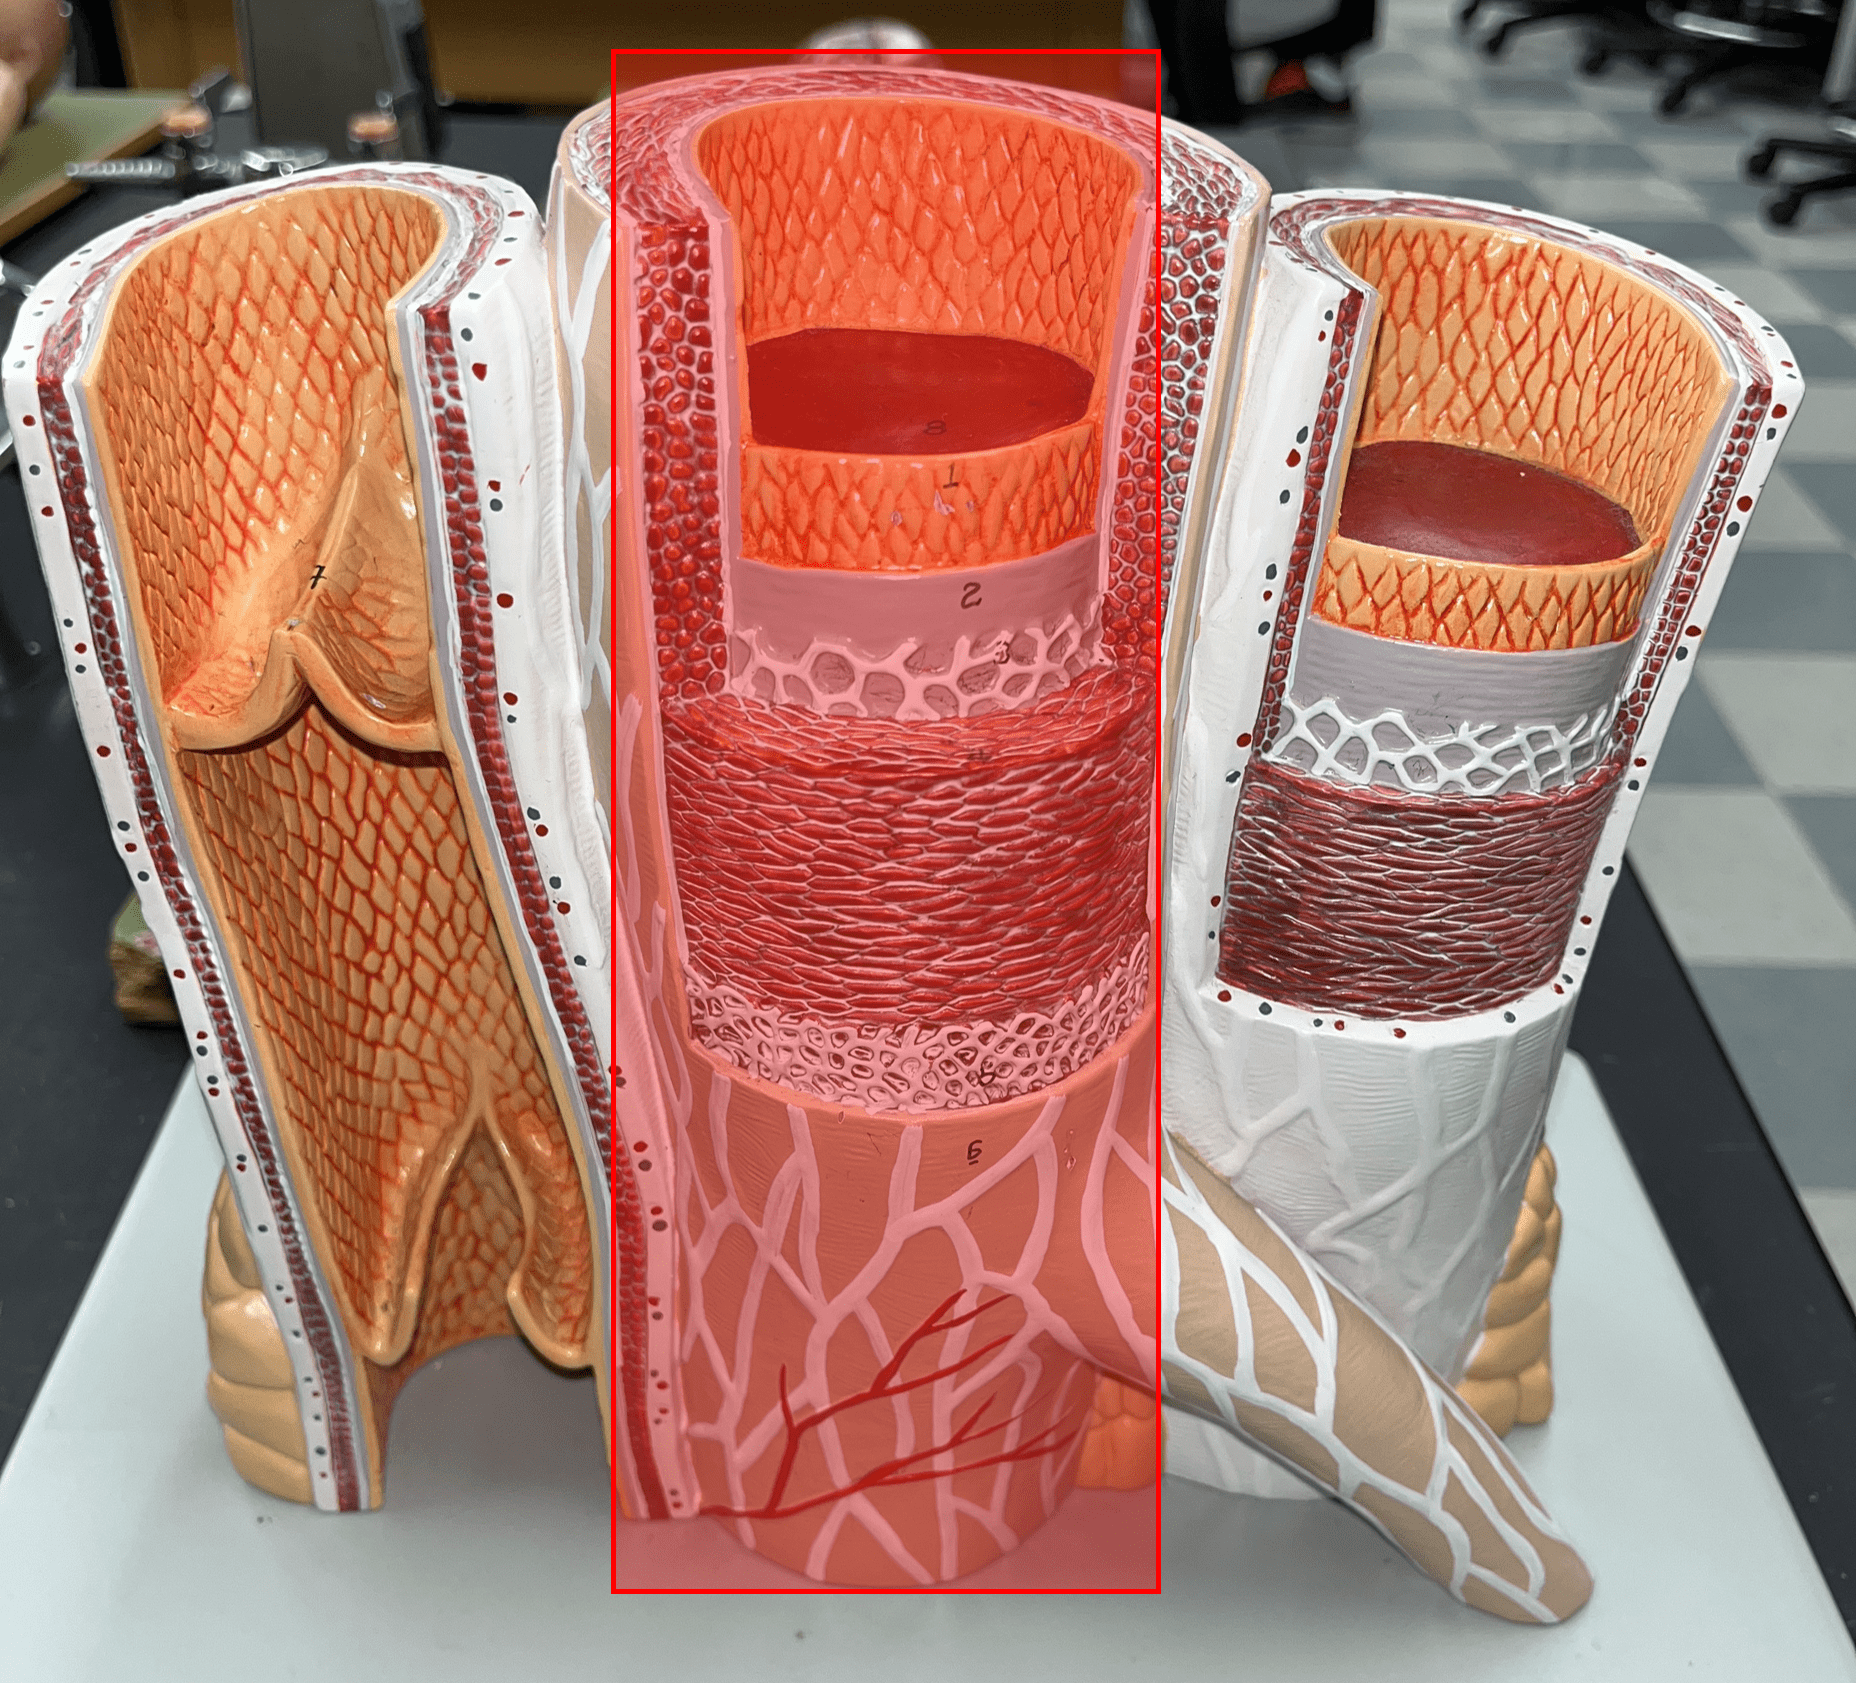

|---|

No study sessions yet.

104 Terms

1

New cards

artery